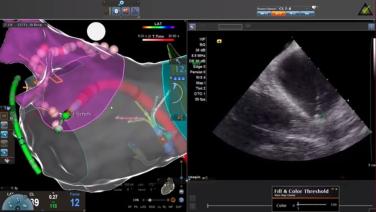

Identifying Left Atrial Anatomy using Intracardiac Echo for Transseptal Puncture with James Brian Deville, MD